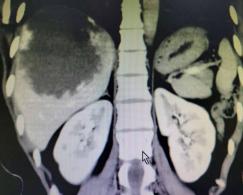

(术前VS术后的影像图)

术中见肝血管瘤巨大,位于右肝6、7、8段,左肝2、3段,且右肝的肿块压迫肝中静脉。